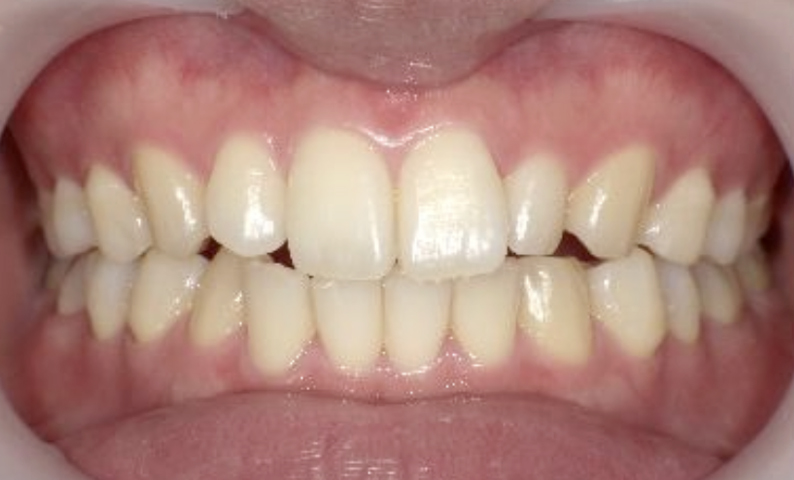

症例_024 上顎だけの部分矯正

治療期間:7ヶ月金額:30万円+税女性前歯のガタガタ上の前歯だけ

| Before | After |